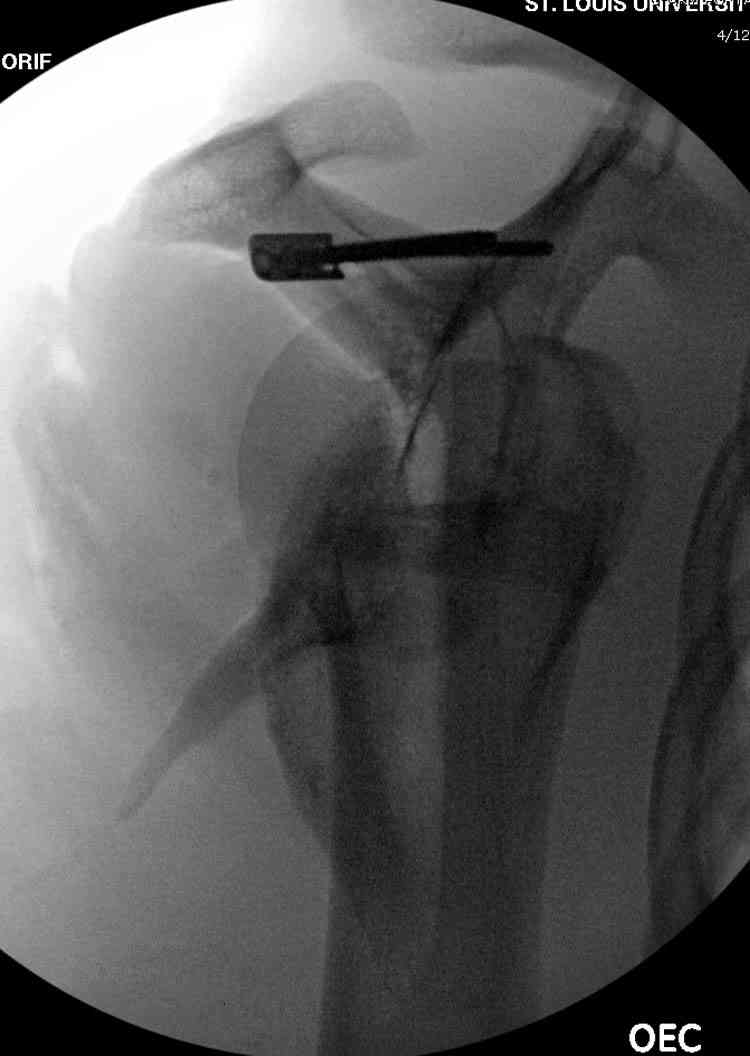

На снимке (№6 компьютерная томограмма и 3D №7) перелом клювовидного отростка.

Передним дельтопекторальным Bankart доступом намного легче провести фиксация отростка, но тогда репозиция и фиксация колонн затрудняется, поэтому был применен стандартный Judet задний доступ.

Репозицию смогли сделать пальцами через щель между

шейкой и телом лопатки (последний 3D снимок)

Двумя шурупами сзади на пластине (вместе шайбы)

провели удержание репозиции, а фиксацию провели

следующим косым шурупом.

Последующие этапы на снимках.